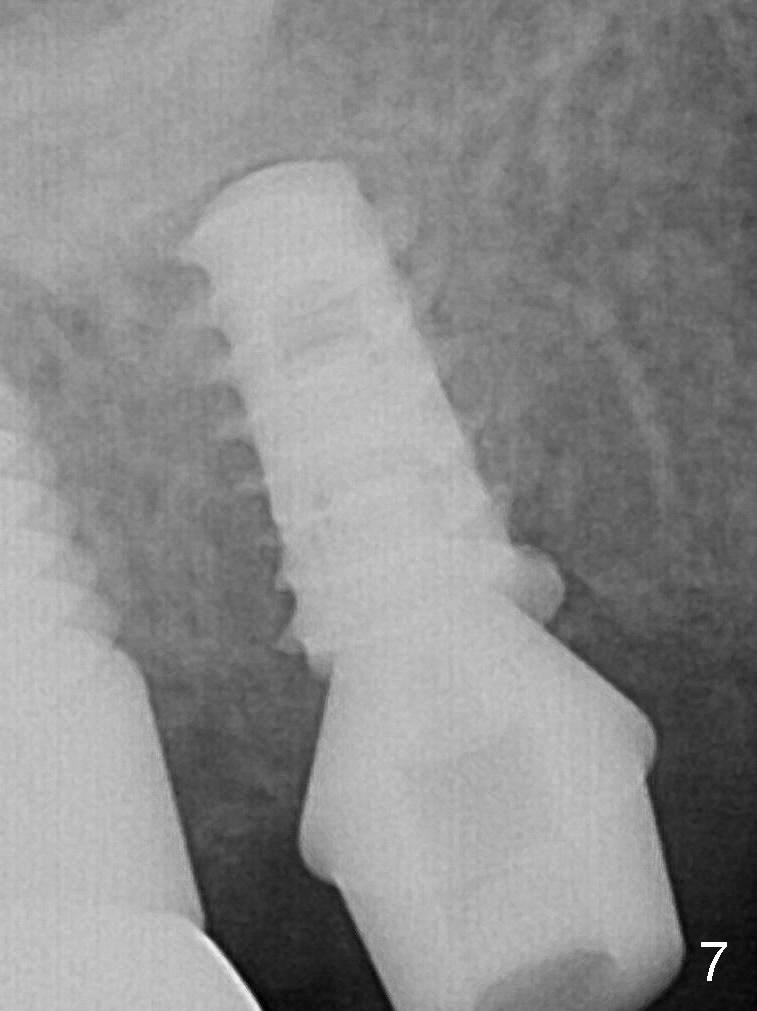

The patient returns with chief complaint of crown is loose with pain 2 months postop (Fig.7). Under local anesthesia, the provisional is removed. The gingiva is erythematous. The implant has mobility. A healing abutment is placed (6x2 mm). Probably a large implant should have been placed.